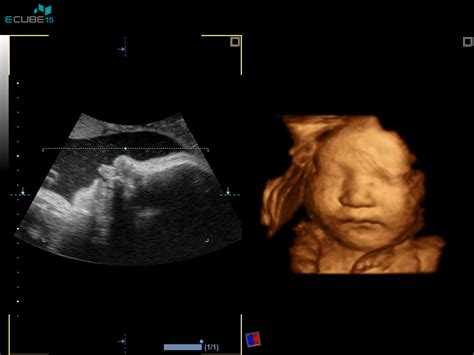

Nuhalna svetlina, prostor napolnjen s tekočino na vratu ploda, ki se nahaja med hrbtenico in kožo, predstavlja enega od najpomembnejših ultrazvočnih pregledov v zgodnji nosečnosti. Ta preiskava, izvedena med 11. in 13. tednom ter šestimi dnevi nosečnosti, ko plod meri med 45 in 84 mm od temena do trtice, ponuja dragocene vpoglede v potencialna kromosomska odstopanja. Z izmero debeline tekočinske kolekcije na vratu otroka lahko zdravniki sklepajo na možnost kromosomskih okvar. Čeprav kar 70 % otrok s kromosomskimi okvarami kaže povečano nuhalno svetlino, je pomembno razumeti, da to ni absolutno pravilo, zato se pri presejanju upoštevajo še drugi ključni dejavniki.

Postopek Meritve Nuhalne Svetline

Meritev nuhalne svetline se izvaja z ultrazvočno preiskavo, ki običajno poteka skozi trebušno steno, v redkih primerih pa se lahko uporabi tudi vaginalni ultrazvok. V času meritve je plod pogosto zelo živo gibljiv, kar omogoča natančno oceno. Med pregledom zdravnik izmeri plod od temena do trtice (CRL - Crown-Rump Length), oceni razvoj okončin, trebušne stene, hrbtenice, glavice in njenih delov, možganov, želodca ter preveri prisotnost mehurja, ki bi ga po 12. tednu nosečnosti morali vedno videti, če ledvici delujeta pravilno. Prav tako se prešteje število žil v popkovini, oceni položaj posteljice in količina plodovnice.

Velikost nuhalne svetline se spreminja glede na dolžino ploda. Če je plod dolg 45 mm, je normalna velikost nuhalne svetline med 1,2 in 2,1 mm. Ko plod doseže dolžino 84 mm, se normalna velikost giblje med 1,9 in 2,7 mm. Vrednost, ki presega 3,5 mm, se nahaja nad 95. percentilo in lahko predstavlja znak za povečano tveganje.